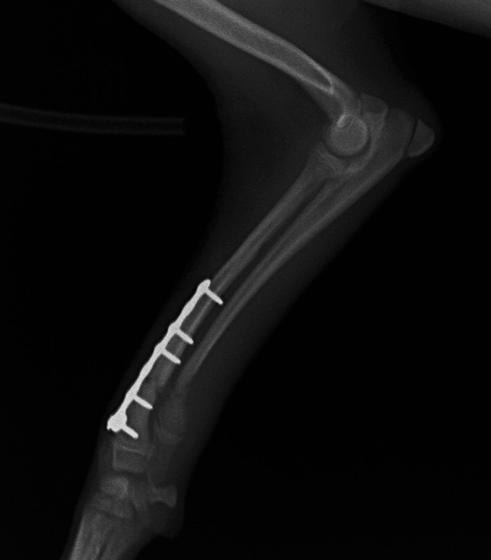

トイプードル 右遠位橈尺骨短斜骨折のALPSによる内固定

Locking Compression Plate

LCPは、スクリュー(ネジ)とプレート(金属の板)をロックする特殊な構造により骨折部位を固定する新しい世代のプレートシステムです。ひとつのホールでロッキングスクリューとスタンダードスクリューの使用を選択できるユニークな構造をしているため、骨折断端間の圧迫を目的とした従来型プレート固定法に加え、高い角度安定性を有するロッキングスクリューを用いた固定法の選択が可能です。従来のプレートシステムでは困難だった部分の骨折や癒合不全の症例に高い治療効果をもたらします。

Advanced Locking plate system と Locking compression plate system

当院ではAdvanced Locking plate system(ALPS)と、Locking compression plate system(LCPS)という骨接合法で骨折症例の治療を行っています。